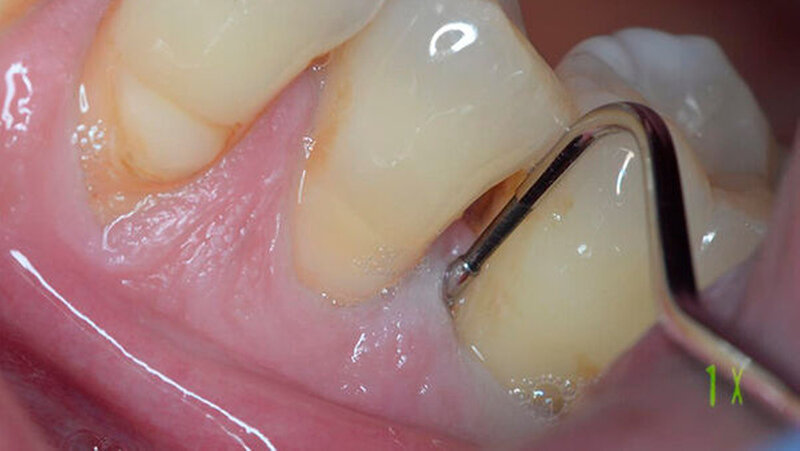

Ein 51-jähriger sportlich muskulöser Patient mit kariesfreiem Gebiss stellte sich zur konsiliarischen Untersuchung vor einer Operation der Kieferhöhle vor. Auf dem OPT imponieren der im Oberkiefer deutlich erkennbare horizontale Höhenverlust mit starker vertikaler Komponente in Regio 15/16 sowie der im Unterkiefer starke vertikale Knochenverlust in Regio 36. Allgemeinerkrankungen oder Medikationen wurden anamnestisch verneint.

Die CT-Aufnahmen zeigen eine deutliche bis zum Orbitaboden heranreichende Totalverschattung der rechten Kieferhöhle. In Höhe des Zahns 16 zeigen sich periradikuläre Rarefikationen als Hinweis auf eine aggressive lokale Parodontitis.